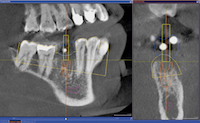

La corrélation de ces données avec les informations 3D issues de l’imagerie radiologique de type « cone beam » permet de réaliser une planification implantaire idéale.